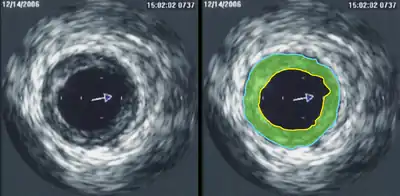

Intravascular ultrasound (IVUS) uses a specially designed catheter with a miniaturized ultrasound probe attached to its distal end, which is then threaded inside a blood vessel. The proximal end of the catheter is attached to computerized ultrasound equipment and allows the application of ultrasound technology, such as a piezoelectric transducer or capacitive micromachined ultrasonic transducer, to visualize the endothelium of blood vessels in living individuals.[11]

In oncological practice of medical contrast ultrasonography, clinicians use 'parametric imaging of vascular signatures'[72] invented by Dr. Nicolas Rognin in 2010.[73] This method is conceived as a cancer aided diagnostic tool, facilitating characterization of a suspicious tumor (malignant versus benign) in an organ. This method is based on medical computational science[74][75] to analyze a time sequence of ultrasound contrast images, a digital video recorded in real-time during patient examination. Two consecutive signal processing steps are applied to each pixel of the tumor:

- calculation of a vascular signature (contrast uptake difference with respect to healthy tissue surrounding the tumor);

- automatic classification of the vascular signature into a unique parameter, the latter coded in one of the four following colors:

- green for continuous hyper-enhancement (contrast uptake higher than healthy tissue one),

- blue for continuous hypo-enhancement (contrast uptake lower than healthy tissue one),

- red for fast hyper-enhancement (contrast uptake before healthy tissue one) or

- yellow for fast hypo-enhancement (contrast uptake after healthy tissue one).

Once signal processing in each pixel is completed, a color spatial map of the parameter is displayed on a computer monitor, summarizing all vascular information of the tumor in a single image called a parametric image (see last figure of press article[76] as clinical examples). This parametric image is interpreted by clinicians based on predominant colorization of the tumor: red indicates a suspicion of malignancy (risk of cancer), green or yellow – a high probability of benignity. In the first case (suspicion of malignant tumor), the clinician typically prescribes a biopsy to confirm the diagnostic or a CT scan examination as a second opinion. In the second case (quasi-certain of benign tumor), only a follow-up is needed with a contrast ultrasonography examination a few months later. The main clinical benefits are to avoid a systemic biopsy (with inherent risks of invasive procedures) of benign tumors or a CT scan examination exposing the patient to X-ray radiation. The parametric imaging of vascular signatures method proved to be effective in humans for characterization of tumors in the liver.[77] In a cancer screening context, this method might be potentially applicable to other organs such as breast[78] or prostate.